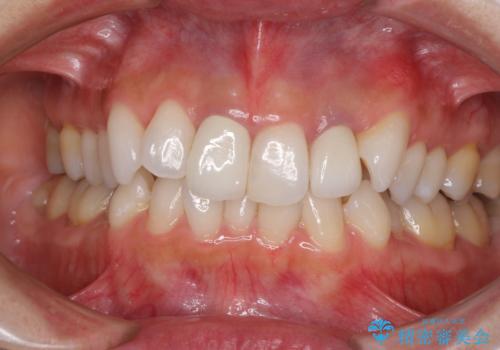

- 20年ほど前に被せた前歯のメタルボンドクラウンの色合いを気にして来院された患者様です。

2歯をオールセラミッククラウン(ジルコニアクラウン)にて補綴することとしました。

裏打ちが金属の場合、どうしても金属色を遮蔽しないとならないため、透明感のない色合いとなってしまいます。

土台の金属はグラスファイバーを含有したものに、クラウンの土台は強化セラミックとすることで、自然な前歯に仕上がりました。